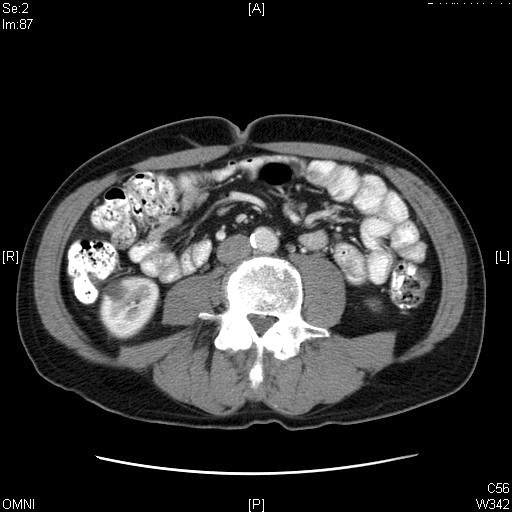

Distinguish Small from Large Intestine. Click the image for labeling.